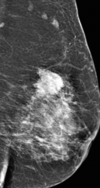

Q

Dx

A

Mastitis